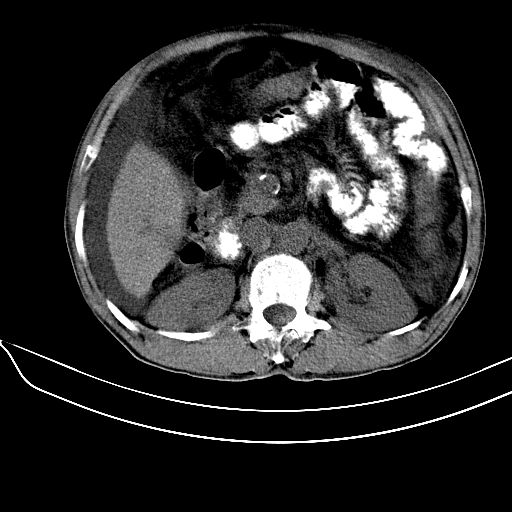

考虑:1、肝硬化、腹水;

2、门脉主干壁钙化(血吸虫所致);

3、脾广泛钙化(原因同上);

肝硬化、腹水; 门脉主干壁钙化,脾广泛钙化;首先考虑血吸虫所致.

肝硬化.腹水.门脉主干壁钙化.脾脏广泛钙化,首先考虑血吸虫所致.